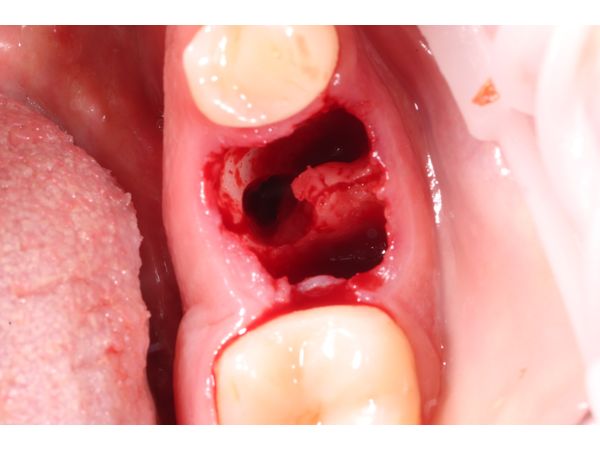

При осмотре слизистая оболочка в области зуба 3.6 покрасневшая, без скопления жидкости. Коронковая часть разрушена кариесом до уровня десны.

- зуб разделили на сегменты и удалили;

- дезинфицировали лунку;